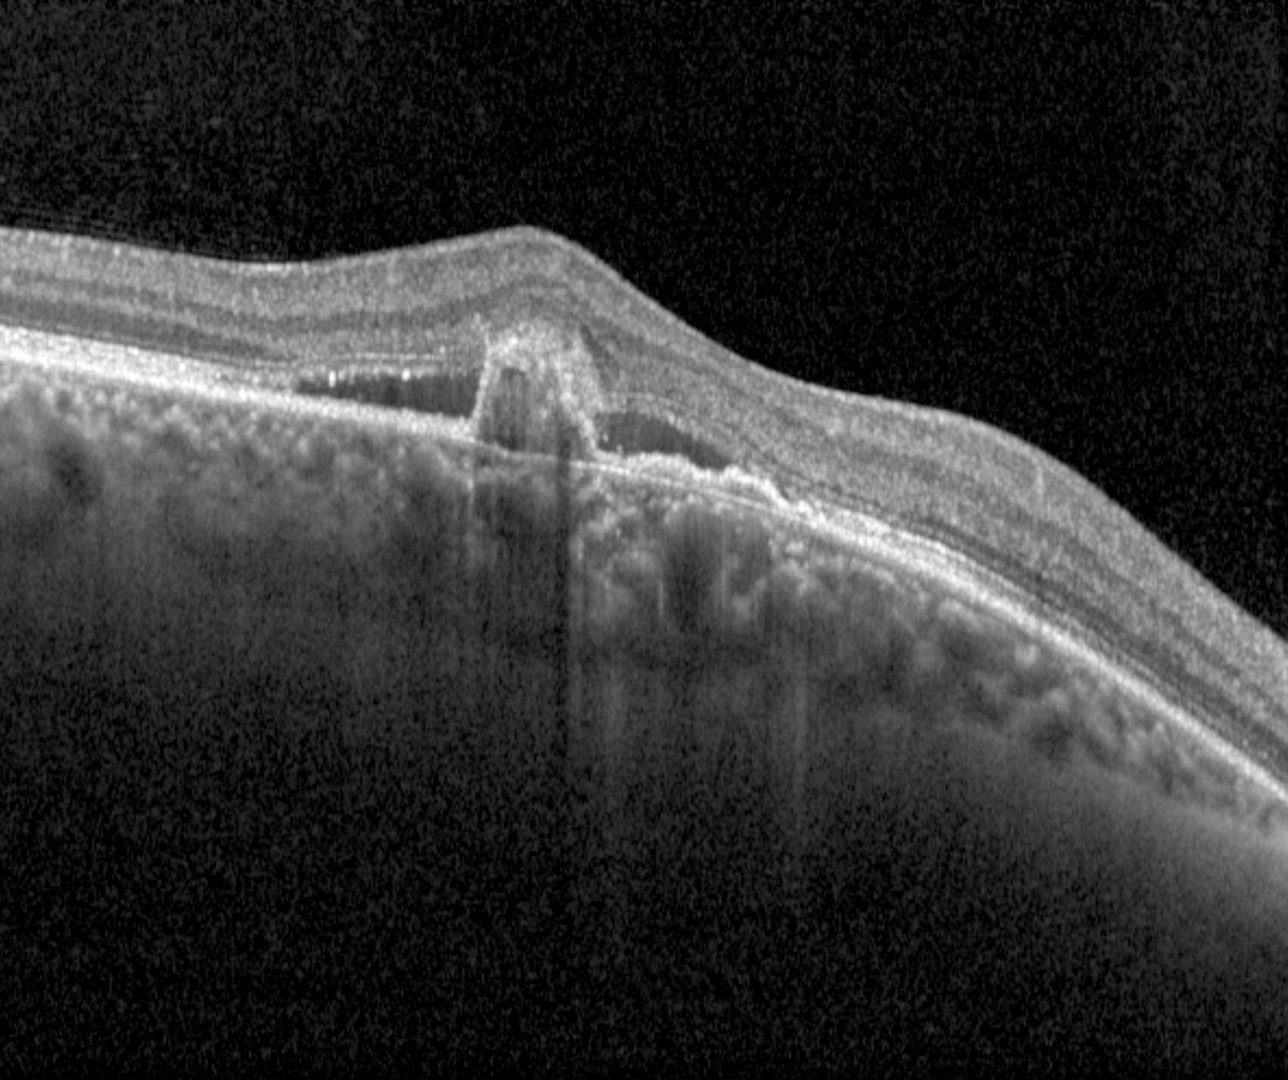

OCT shows multilobular PEDs with the peaked, thumb-like or notched component corresponding to the polypoidal lesion and the flat irregular PED harbours the type 1 neovascularisation.